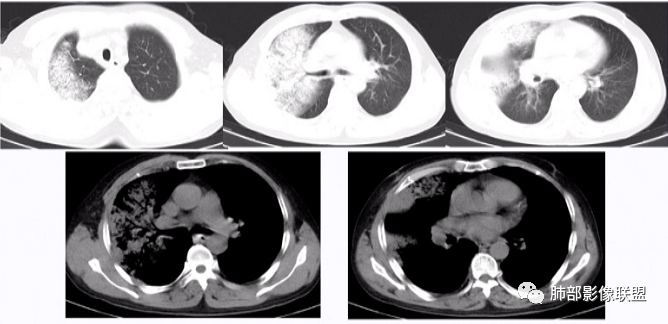

张延军: 左肺上叶前段沿支气管束周围见实变影,边缘收缩,界不清,内见小空洞影,与支气管相通,病变周围散在结节及斑片状高密度影,树芽征(+),中年男性,类似结核中毒症状,感染指标升高,考虑NTM,结核代排。

joyzhy:中年男性,咳嗽咳痰,炎性指标升高。影像,左肺上叶片状实变,部分平直,部分内收,支气管血管束增厚,头孢类治疗后效果不佳。考虑非典型肺炎,支原体?鉴别:吸入性肺炎

衡妈: 实变+支气管充气征,可见支气管壁增厚,病灶边缘模糊磨玻璃。我没有看到树芽;NTM 一般要有背景 比如支扩

张丽红: 有发热,咳嗽呼吸道感染症状。左肺上叶斑片影,内部支气管走行自然。右肺也有散在斑片影。考虑非结核分枝杆菌,结核

青藤之凉: 支原体肺炎的影像特征相对比较明显。有支气管壁增厚、支气管扩张样改变、支气管充气征。小叶小结节,有点状或者斑片状的浸润影、有实变影,表现为树芽征、树雾气征。

影像学特点:①支气管壁增厚、支气管周围炎。②腺泡结节、树芽征、树雾征(见病例1)。③结节融合,大片实变,部分边缘收缩。④分布上较广泛 。